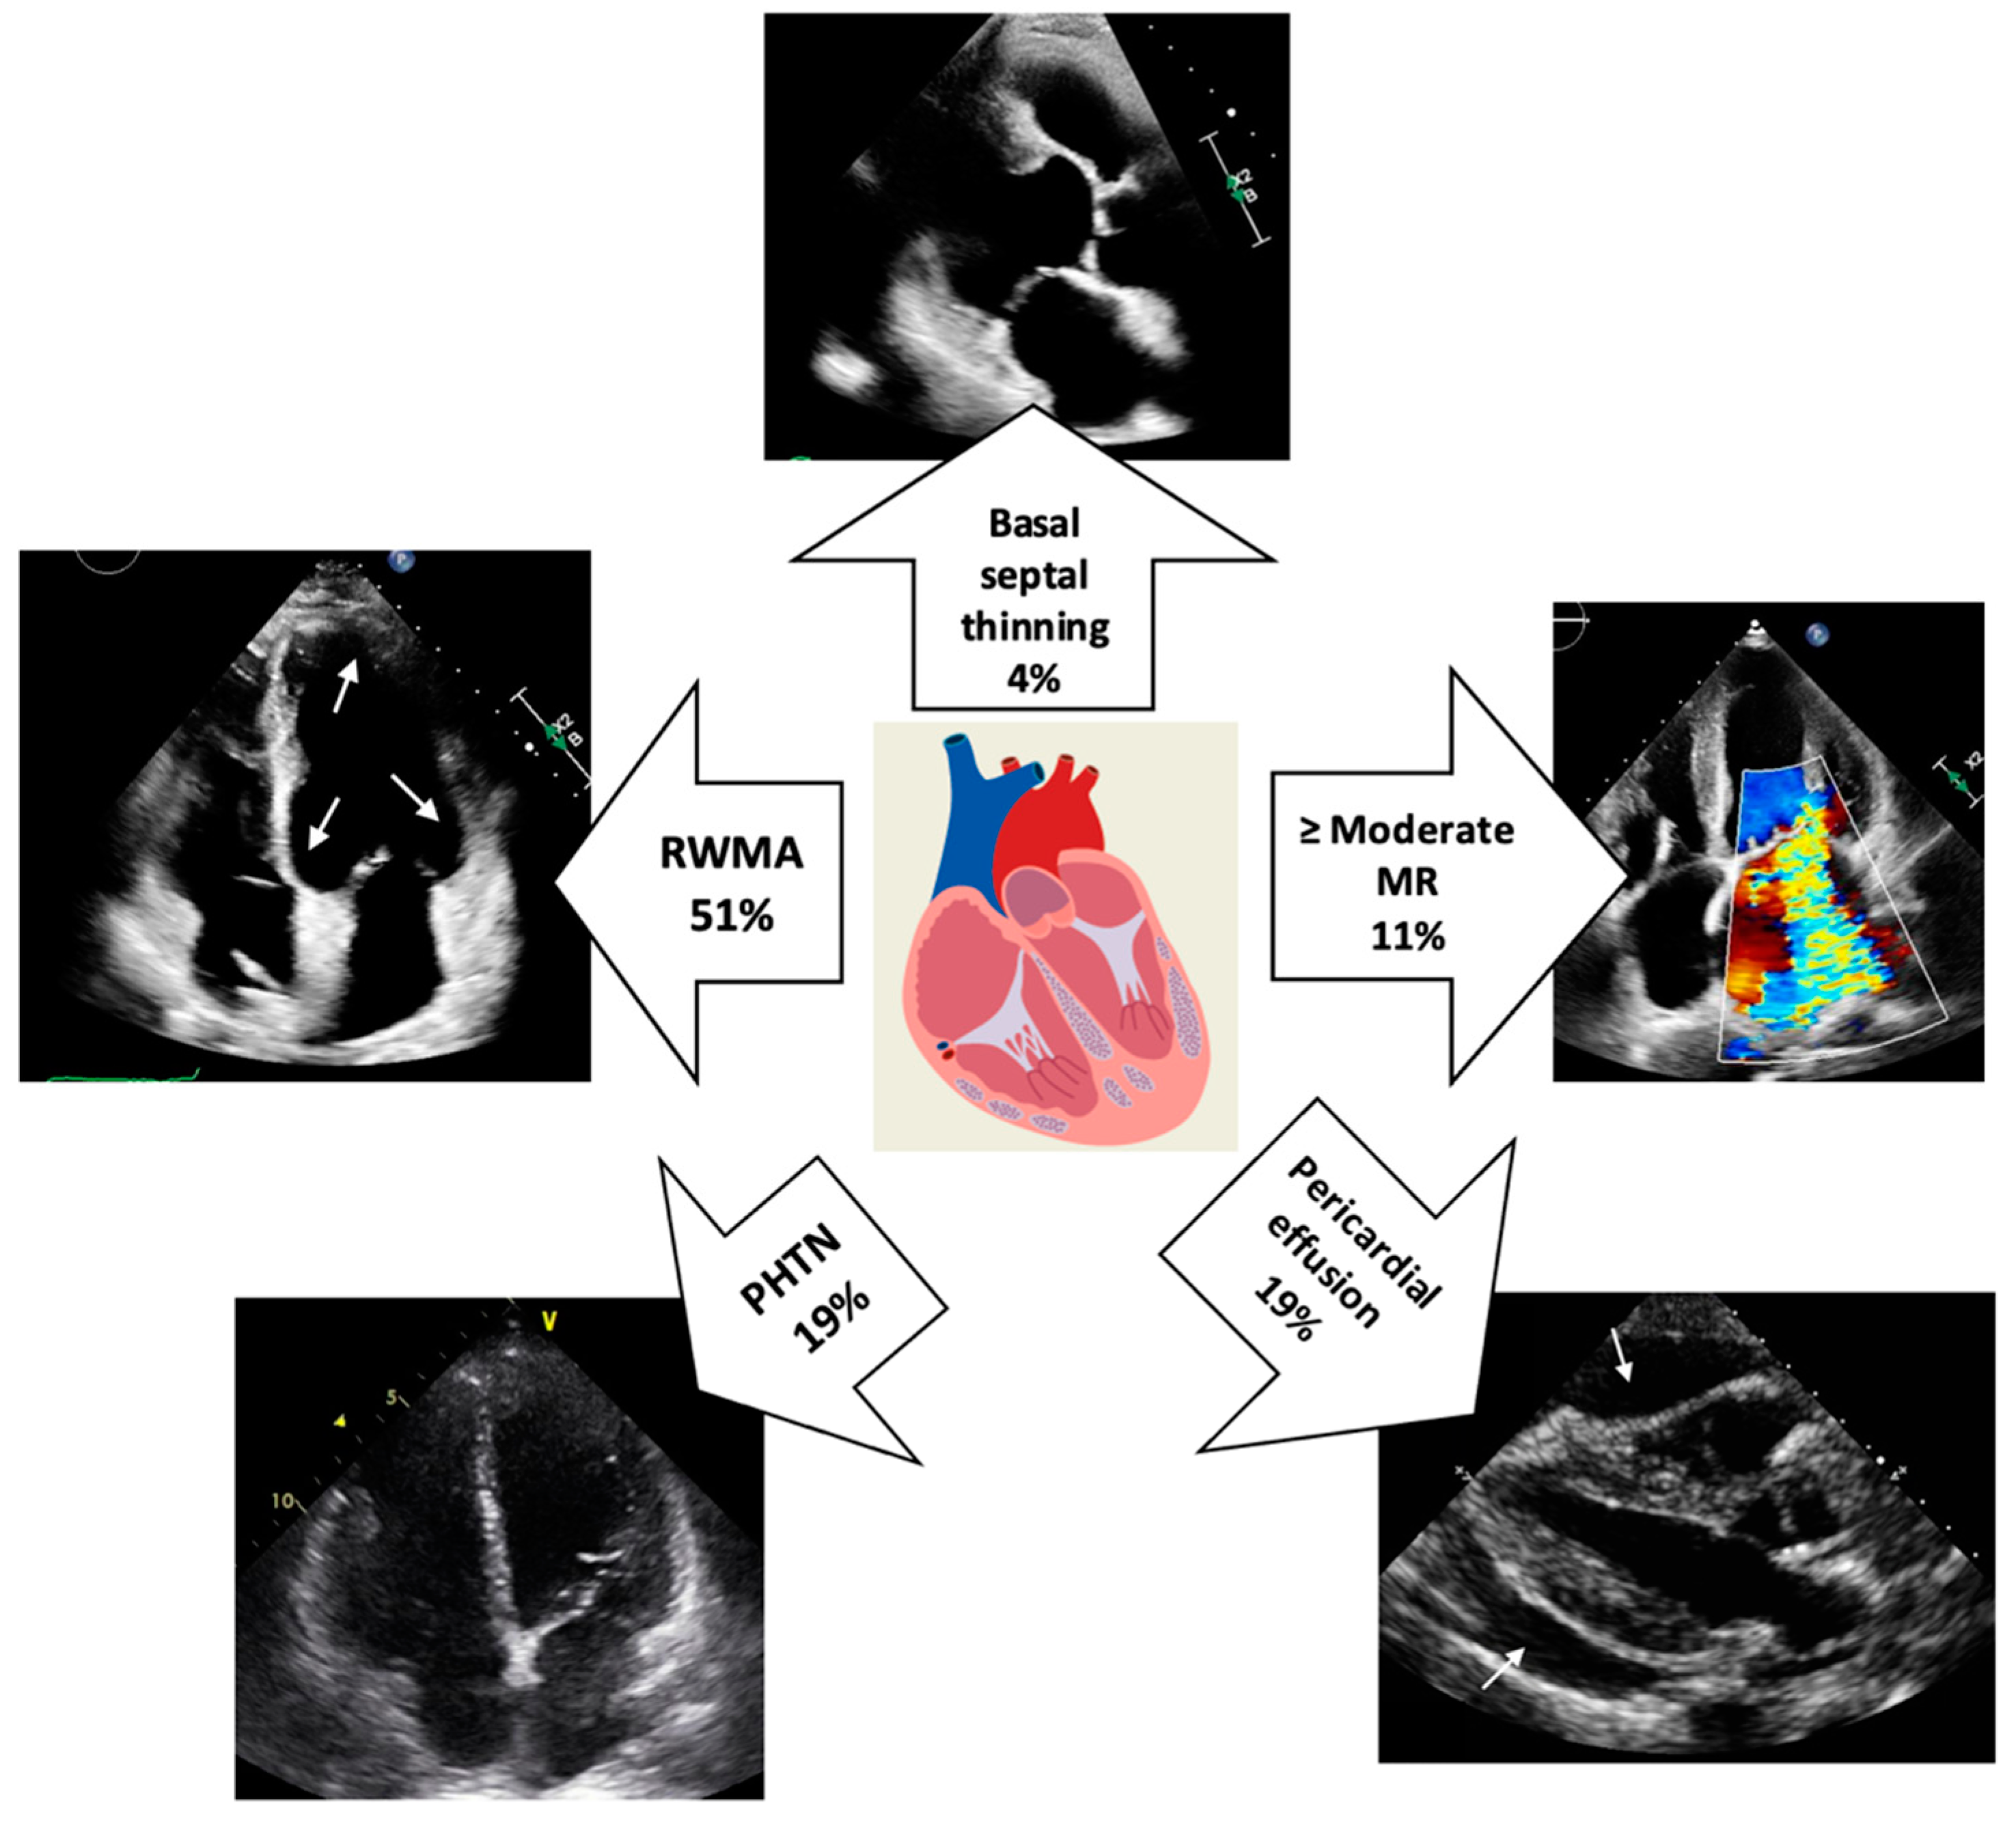

Several TTE abnormalities increase the likelihood of a patient with systemic sarcoidosis having cardiac involvement and should trigger LGE-CMR ± FDG-PET to confirm the diagnosis (Figure 1, central illustration). These include RWMA particularly when associated with wall thinning in a non-coronary distribution, most commonly seen in the basal septal region. Other abnormalities may include increased myocardial echogenicity and RV free-wall aneurysm formation.

Figure 1.

Central illustration: Prevalence of echocardiographic abnormalities in cardiac sarcoidosis. The white arrows indicate multifocal RWMA (top-left image) and global pericardial effusion (bottom-right image). (MR = mitral regurgitation; PHTN = pulmonary hypertension; RWMA = regional wall motion abnormality).